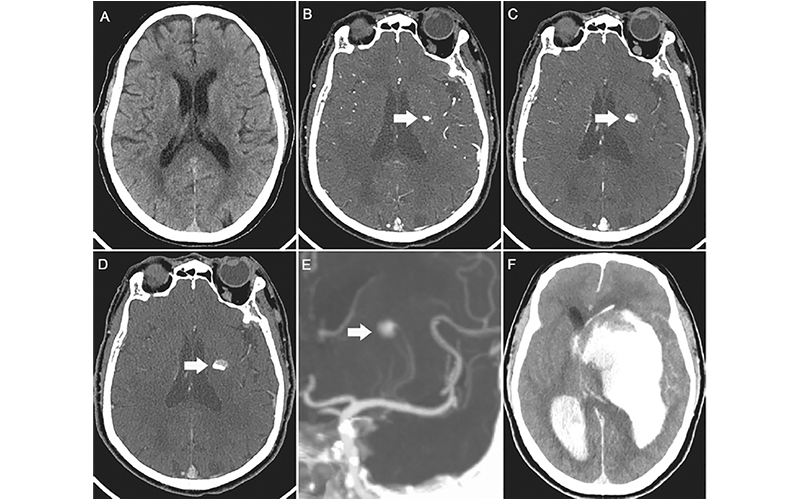

Второе место заняла ничья между двумя статьями. Первый, «КТ продолжающегося внутримозгового кровоизлияния», был сделан Чун Ма и И Чжоу с визуализацией, которая зафиксировала быстрое развитие прогрессирующего внутримозгового кровоизлияния у 73-летнего мужчины.

2-е место, занявшее 1 место в топе изображений 2022 г.

Изображения 73-летнего мужчины с острой левосторонней слабостью. (A) Осевое неконтрастное КТ-изображение головы не показывает внутримозгового кровоизлияния. (B) КТ-ангиограмма в артериальной фазе, полученная через 192 секунды после введения контрастного вещества, демонстрирует очаговое усиление в левых базальных ганглиях (стрелка). (В, Г) КТ-ангиограммы, полученные во вторую (В) и третью (Г) фазы, с задержкой 39 секунд и 38 секунд соответственно, выделяют активное распространение внутримозгового кровоизлияния с уровнем контраста крови (стрелки). (E) Проекционное изображение максимальной интенсивности в коронарной области показывает, что кровотечение локализовалось вблизи дистальных концов лентикулостриарных артерий (стрелка). (F) Последующее бесконтрастное КТ-изображение, полученное через 1 час после третьей фазы КТ-ангиограммы, показывает массивное увеличение гематомы, внутрижелудочковое кровоизлияние, гидроцефалию, и субфальцинозная грыжа.